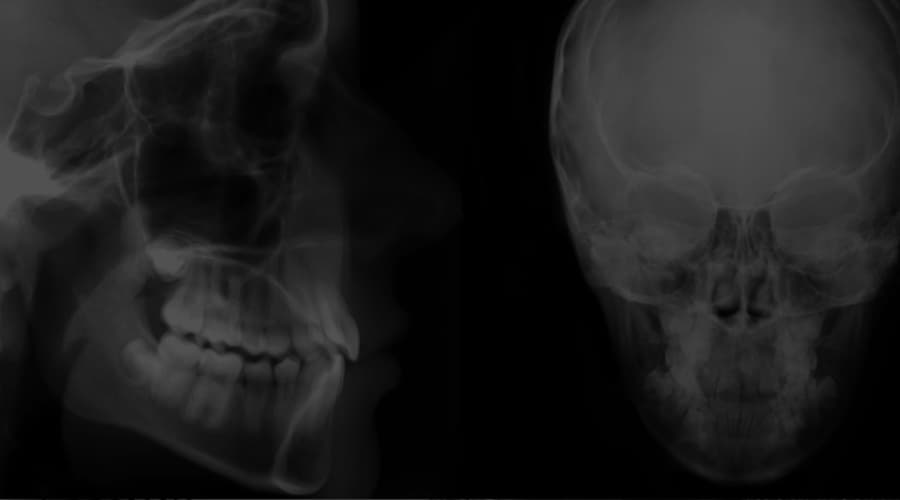

OCCLUSION Condylar Axis Movement from Centric Relation to MIP What Is Centric Relation In Dentistry The concept of cr emerged due to the search for a. centric relation (cr) is the maxillomandibular relationship in which the condyles articulate with the thinnest avascular portion of their. this article reviews the definitions of centric relation (cr) in dentistry and prosthodontics from 1929 to 2010, and. centric relation (cr) is the most controversial concept in. What Is Centric Relation In Dentistry.